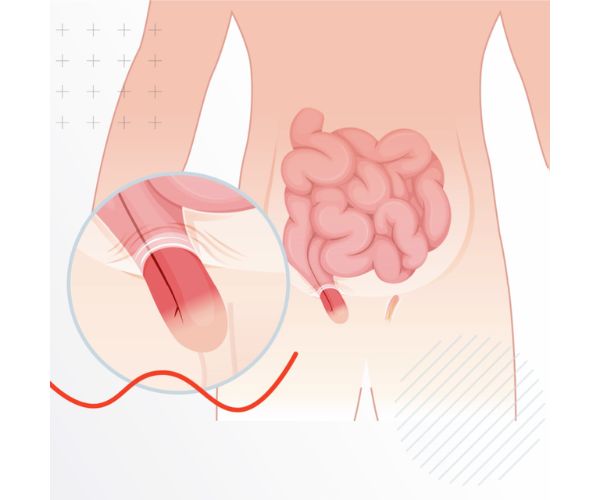

العلاقة بين الفتق الإربي والانتصاب والجماع

كشفت الدراسات وجود ارتباط بين الفتق الإربي وبعض المشكلات الجنسية، خاصة ضعف الانتصاب أو الألم أثناء العلاقة الزوجية. ويرجع ذلك إلى تأثير الفتق أو التورم في منطقة الفخذ والأعضاء التناسلية، ما يؤدي إلى الشعور بعدم الراحة أثناء العلاقة.

لكن بعد إجراء العملية واتباع تعليمات الطبيب بدقة، تختفي هذه الأعراض تدريجيًا، ويستعيد المريض القدرة على ممارسة العلاقة بشكل طبيعي بعد اكتمال مرحلة التعافي.